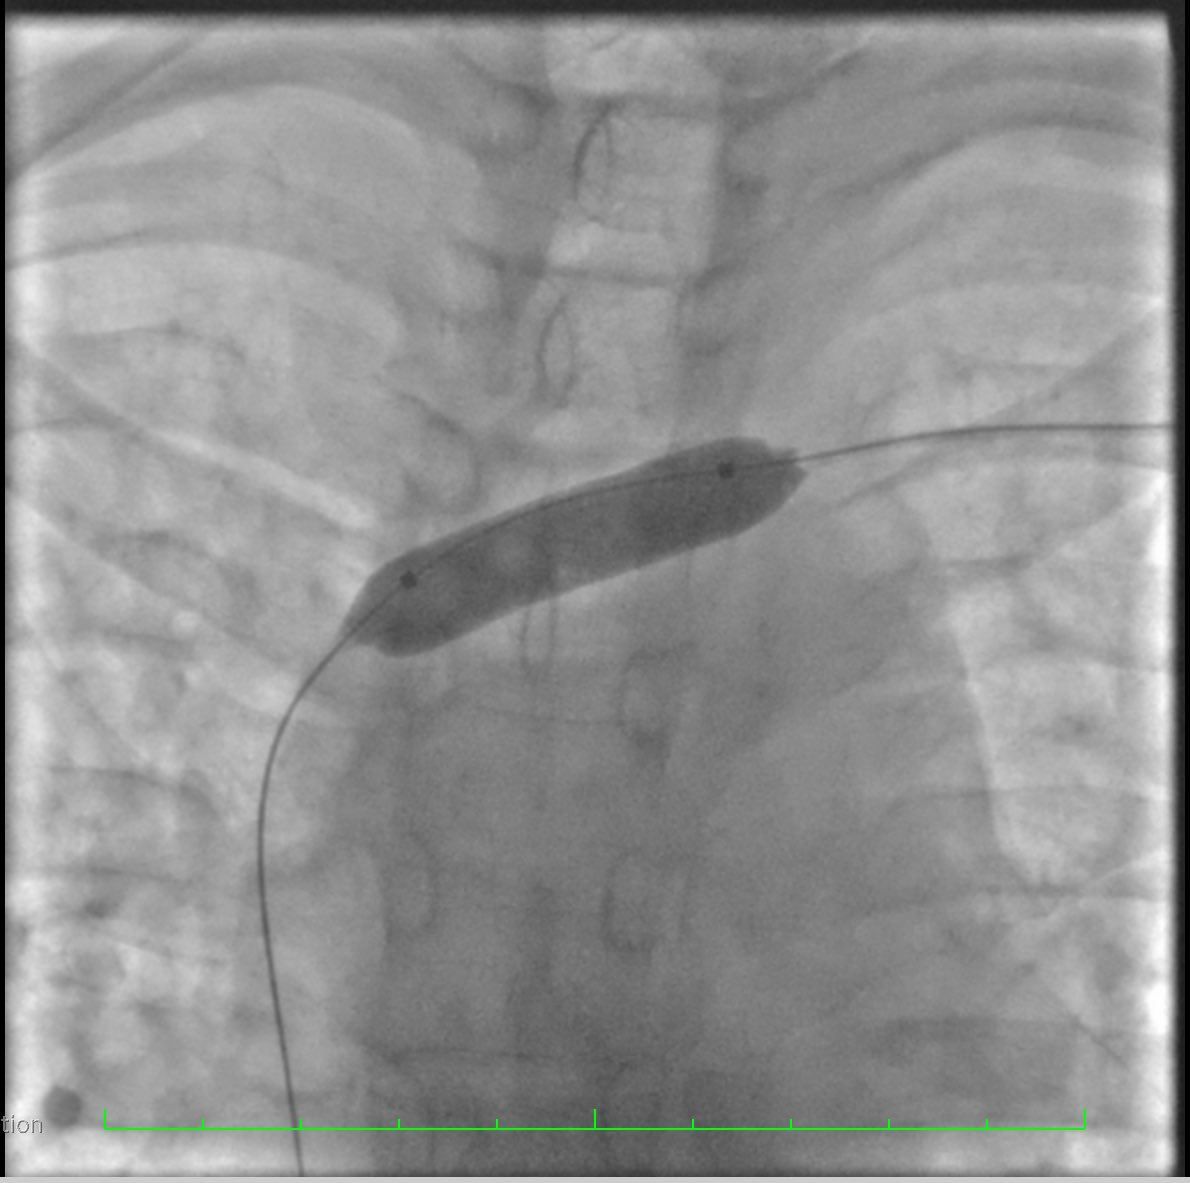

Colocación de Catéter Tenckhoff percútaneo con técnica Seldinger Servicio de Nefrología HGR 46 ✅Menor estancia hospitalaria ✅Menor riesgo de complicaciones ✅Uso temprano de cavidad peritoneal